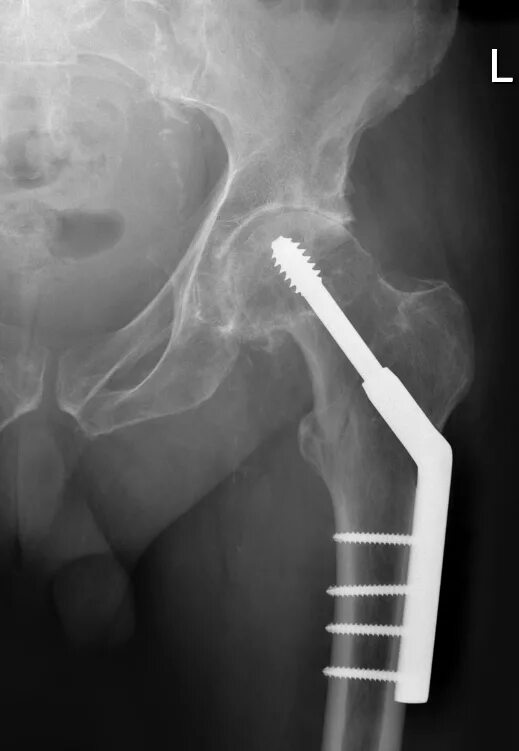

Валик между ног после эндопротезирования тазобедренного сустава